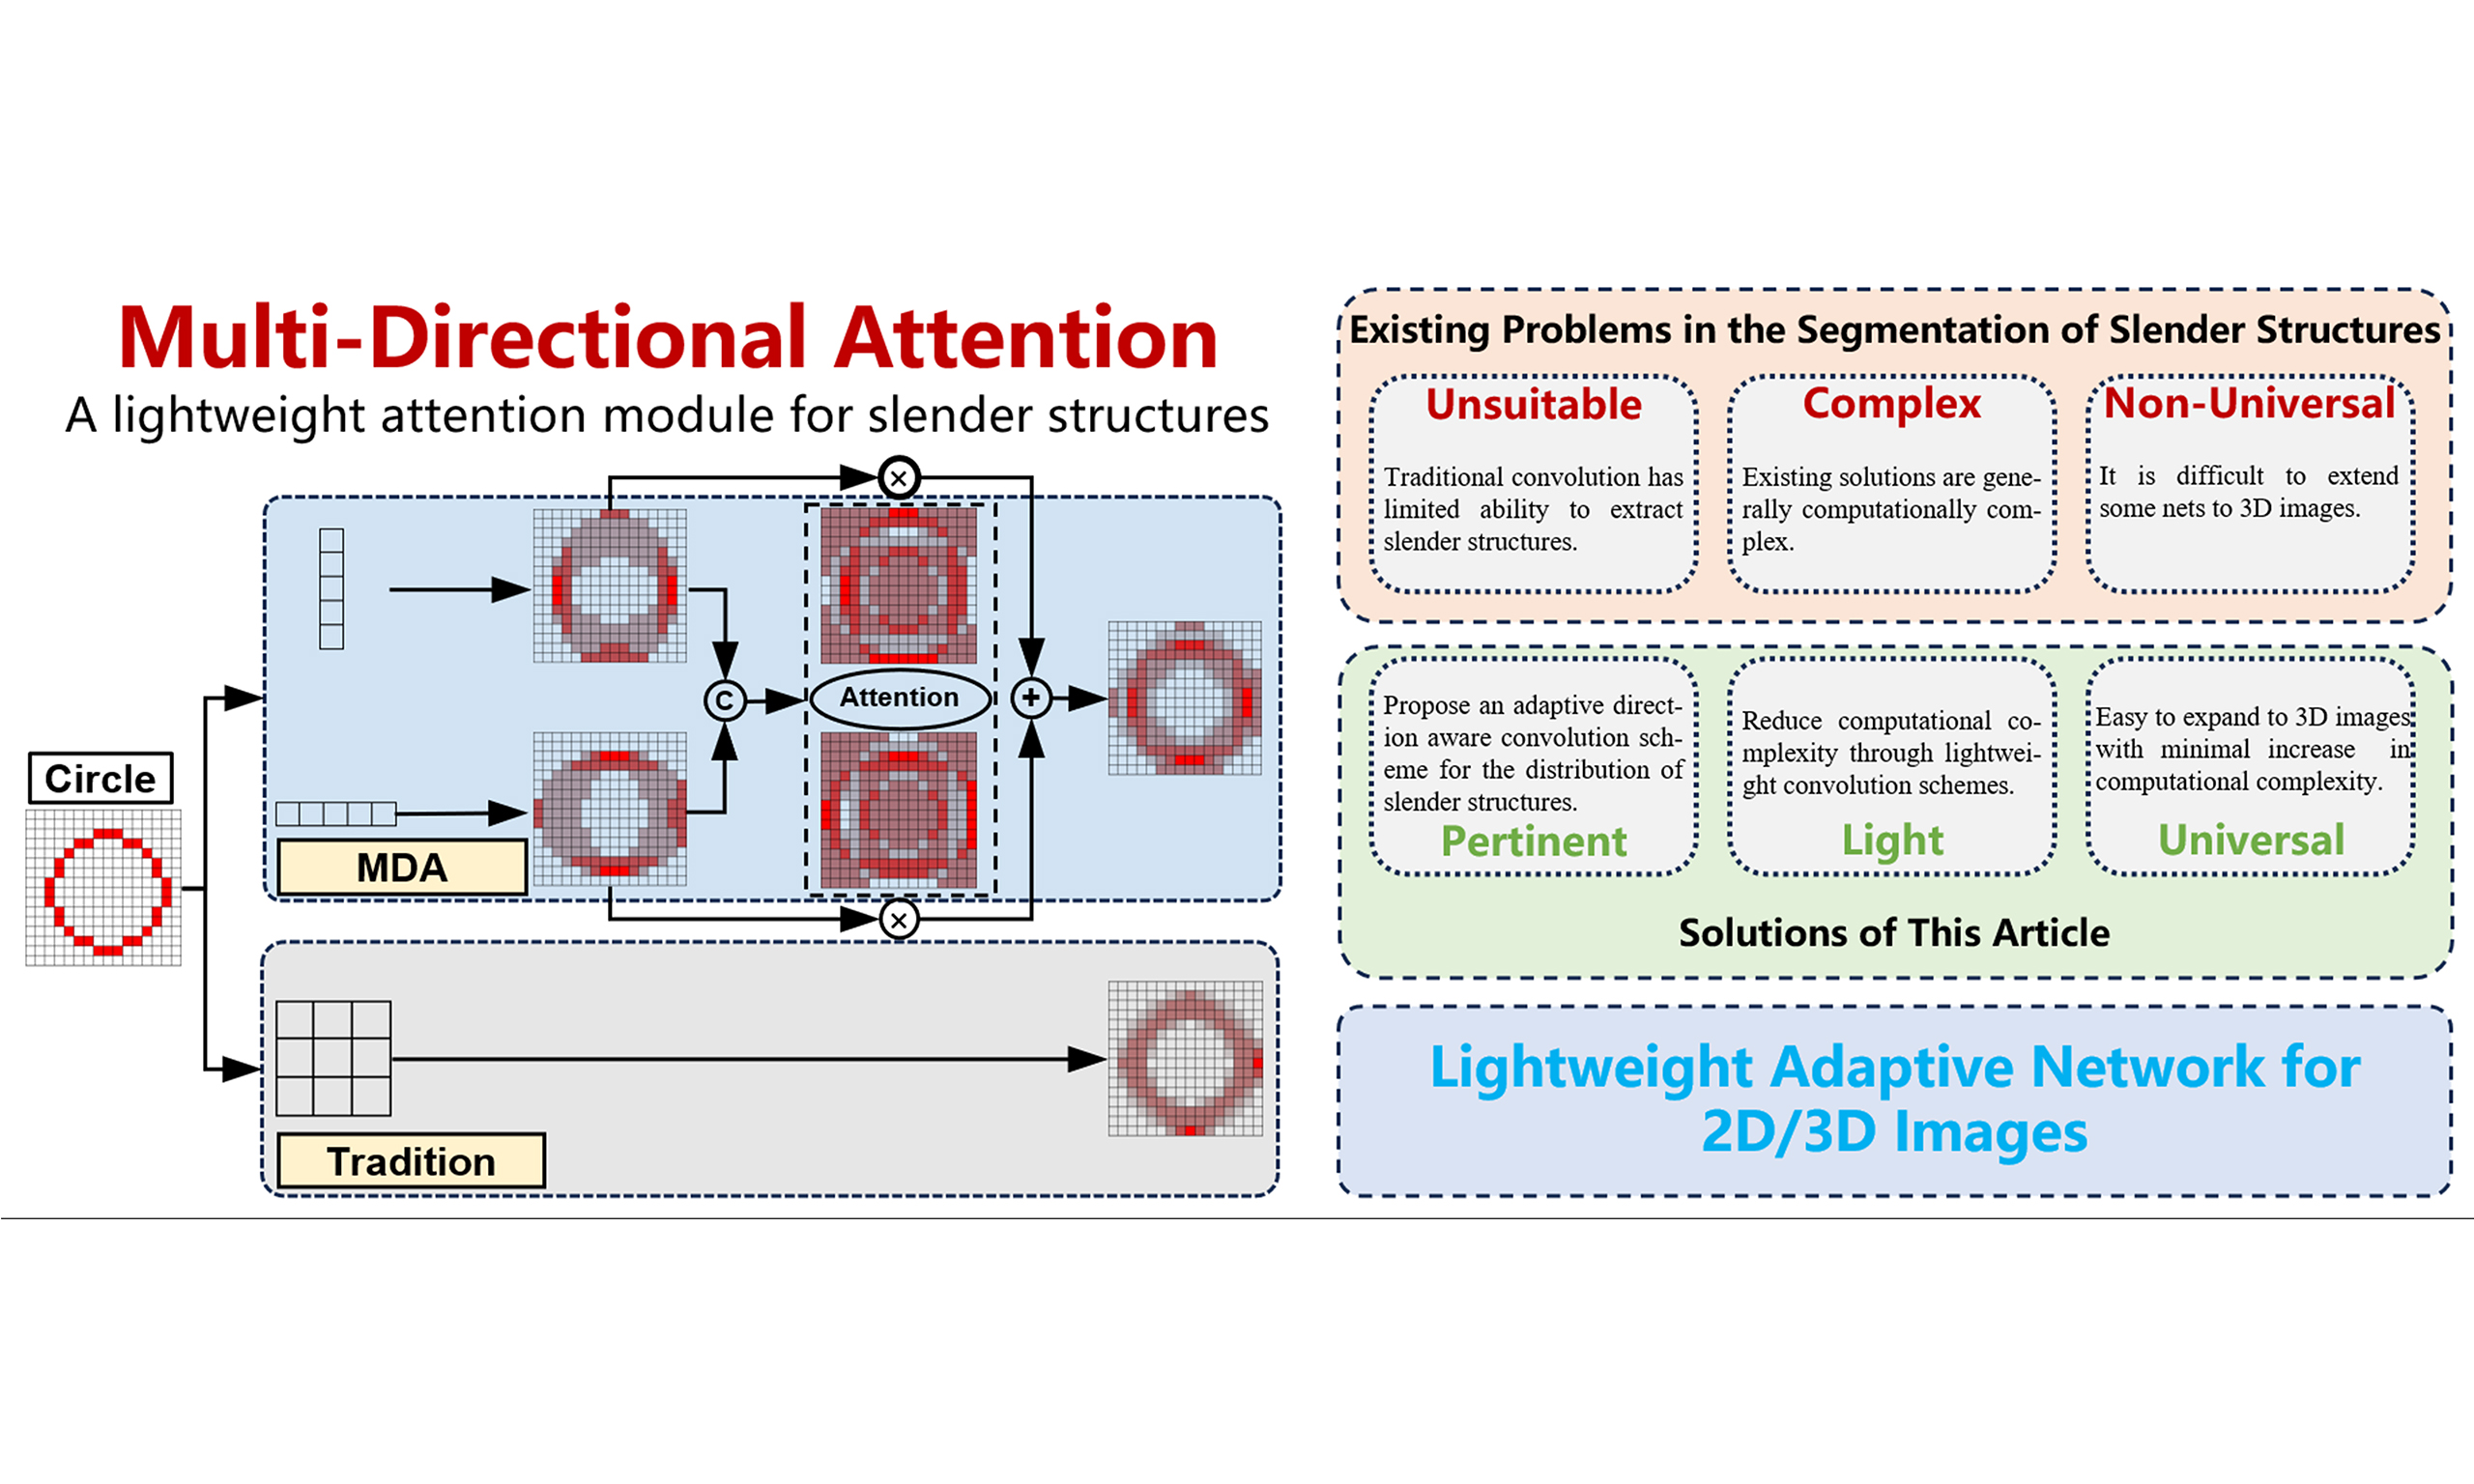

The segmentation of slender structures in images faces challenges of discontinuous segmentation and insufficient recognition. These slender structures, such as arteries and veins, are particularly important in 3D medical images that are sensitive to the computational complexity of segmentation networks. Therefore, in order to balance the computational complexity of the network and adaptive perception of slender structures, this paper proposes a multi-directional attention module for slender structures, which is a lightweight attention module that can be inserted into the encoder or decoder unit. At the same time, we propose a contour loss function to address the class imbalance phenomenon that may arise in the joint segmentation task of slender and ordinary structures. This function improves the balance by converting traditional class mask labels into contour mask labels. The effectiveness of our proposed module has been validated through training on segmentation tasks on 2D and 3D images.

To address the aforementioned challenges, some studies have made improvements to slender structures. We can divide these studies into three dimensions: (1) Improvements from the perspective of convolution itself, such as dilated convolution[2], deformable convolution[3], dynamic snake convolution[4], etc. These convolutions adapt to the shape of the target structure by changing the way of obtaining context; (2) Improvements from the perspective of network architecture, such as all-scale feature fusion[5], dual chain fusion U-Net[6], encoder-dual-decoder-based network[7], graph convolutional networks[8], etc., aim to enhance the perception ability of slender structures by changing the form of the network; (3) Improvements from the perspective of loss functions, such as introducing centerline-Dice similarity measurement[9], geometric measurement[10], etc. These studies have some targeted designs for us to learn from, but some methods that introduce huge computational complexity are not suitable for our applications.

Unlike the above research, in order to target some segmentation application scenarios that require low computational complexity, we propose a lightweight multi-directional attention mechanism on the basic encoder-decoder structure network. By changing the shape of the convolution and adding an attention fusion strategy, this attention mechanism can be well integrated into the encoder-decoder units of the network. In addition, we also propose a low computational complexity contour loss function method, which reduces the impact of class imbalance during training by converting segmentation labels into contour labels. In terms of network architecture, we have also made appropriate modifications to the skip connections and bottleneck layers to better perform feature fusion. To sum up, our contributions are as follows:

In fact, the essence of these convolutions is to break the constraint of weight sharing in convolution kernels, in order to better adapt to the shape of the target structure in the image. Therefore, our multi-directional attention mechanism is designed as follows.

3.2. Multi-directional attention and the units designed based on it

Unlike deformable convolution, which requires learning an offset, we directly design strip-shaped convolution modules in different directions to adapt to offsets representing the direction of slender structures. The attention mechanism we designed and the encoder-decoder module common and multi-direction with residual (CMR) Block integrated on it are shown in Figure 3.

Through this processing mechanism that integrates multi-directional strip convolution results, the multi-directional attention module can combine attention weights to overcome the impact of convolution kernel weight sharing on feature extraction, and better help pixels find the adjacent pixels with the highest correlation in their neighborhood, thus achieving adaptation to slender structures. As shown in the upper right corner of Figure 3, for a circular arc curve that can represent any direction of slender structures, the feature map processed by the multi-directional attention module better preserves the original features of the curve compared to the feature maps of traditional convolution, without being mixed by background pixels. Besides, in order to minimize computational complexity, we introduced the depthwise separable convolution[20] into the module instead of using traditional convolution method.